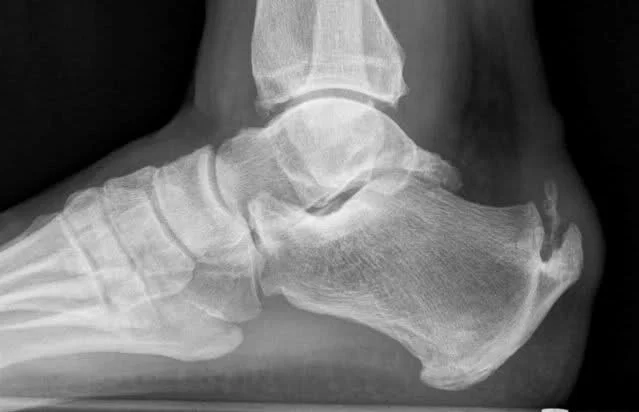

/As we age, bone health becomes increasingly important, especially for women, who are most at risk for bone density issues. Bone spurs or osteophytes are extra growths of the bone that can happen on the edge of any bone. Symptoms can include joint pain, tenderness, swelling and loss of motion in that affected joint. Bone spurs occur most commonly around the joints and can occur in the spine as well. They are not painful but can cause pain when they rub against other bones and nerves. Tendonitis or osteoarthritis are often one of the main causes of bone spurs. In some cases, they are a natural part of aging. Some even cause no symptoms and not even need any treatment. Others require pain medications and surgery.